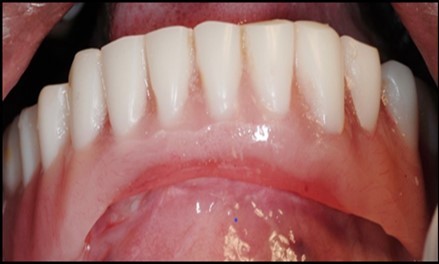

A transferable mark with an indelible pencil is placed on top of each ball abutment and old denture is seated to ideally determine the location for attachment housings. It is followed by preparation of recesses in the intaglio surface of the denture to accommodate the housings (Figure 7B). Lingual vent holes are made for escape of excess acrylic. Placement of nylon processing insert into each of the housings is done with insert seating tool. Figure 8 Seating of the attachment housing onto each ball type abutment is done (Figure 9). Undercuts are blocked out under the housing and soft tissue to prevent acrylic resin from locking the denture onto the abutment. Application of self curing acrylic is done into recessed area and around titanium housings for bonding of the housings to denture. Insertion of denture was done and guiding the patient into proper occlusion with the opposing arch. After the curing of acrylic, denture is removed. Excess acrylic is removed around the housings and lingual vent hole later it is polished (Figure 10). Replace nylon retention insert instead of processing insert into the housings. The insert must seat securely in place and be in level with the housings rim. Overdenture is seated over the ball abutments (Figure 11). Proper instructions have been given to the patient on insertion and removal of prosthesis (Figure 12). The patient was recalled at 1 week, 3 weeks, 3 months, 6 months follow up appointments.

1. Full arch implant supported fixed prosthesis, Implant supported overdentures.14, 15 (Figure 12)

General criteria for survival and success of implants have been used to evaluate the efficacy of immediately loading mandibular implants. For example, survival criteria include how the implant performs, particularly regarding the absence of pain, infection, and paresthesia. Implant immobility and the absence of periimplant radiolucency under radiography are 2 more criteria of implant survivability.6, 7 Success criteria include the additional element of absence of vertical bone loss; specifically, less than 1 mm during the first year and less than 0.2 mm annually thereafter. Granted that success rates for immediatel oading of implants in the edentulous mandible are not as high as rates for the traditional 2-stage approach, conditions nevertheless often warrant the 1-stage surgical option described here.7, 8, 9 (Figure 12).

Using 2 implants and retentive anchors for the retention of a mandibular complete denture is, in terms of immediate costs, one of the most affordable implant procedures. 8, 9, 14 With ideal placement of the implant, the stability of the prosthesis is excellent and the lingual dimensions of the denture can in some cases be reduced to the level of mylohyoid line, providing more space for the tongue and greater comfort than with conventional complete dentures.8, 9, 10, 15 However, if the labial musculature is tense or the amount of attached gingiva is limited, the implants should not be placed too deep or too labially, which might prevent gingival growth over the abutments. In those cases, ball anchor abutments with elevated shoulders can be used to improve implant anatomy.8, 9, 10 (Figure 12).